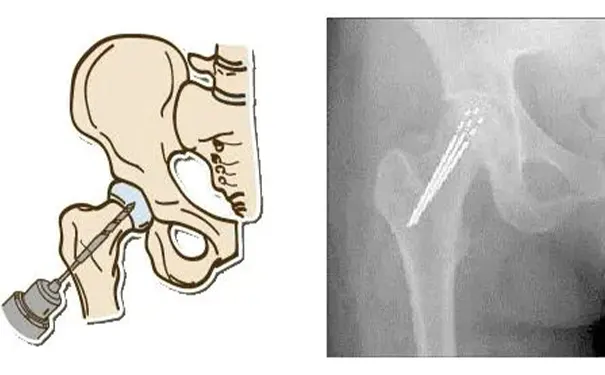

核心减压术:通过在股骨头部钻孔,刺激新血管及健康骨组织生长,重新滋养股骨头。早期患者术后恢复期约 3 个月,多数可脱离辅助工具行走,痛感显著改善。

骨与软骨移植术:从自身或骨库提取健康骨组织与软骨,移植至髋关节受损部位,可与核心减压术配合实施,适用于坏死初期患者,促进健康骨组织及软骨再生。